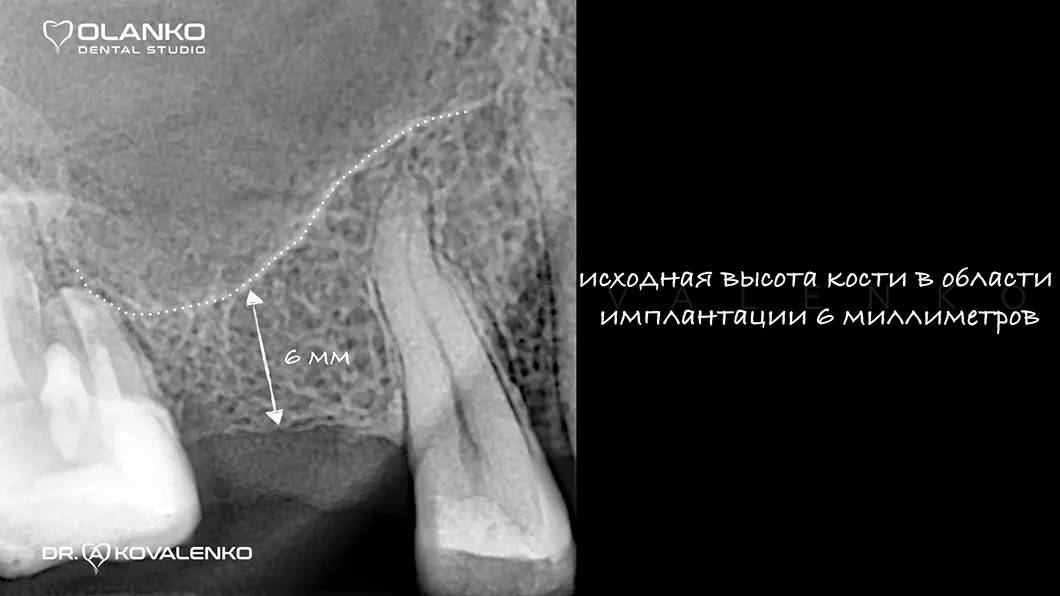

Атрофія - це прогресуюче зменшення кісткової тканини, що супроводжується також і зменшенням ширини та висоти альвеолярного гребеня. Розвивається після видалення зуба і є найпоширенішою перешкодою для встановлення зубного імплантату.

Спеціалісти Olanko dental studio (Оланко) м. Бровари рекомендують проводити операцію по встановленню зубного імплантату в максимально ранній період після видалення проблемного зуба (від 3 до 6 місяців), або використовувати методику імплантації одномоментно з видаленням зуба лише тоді, коли є умови для проведення такої операції. Але якщо зменшення кісткової тканини вже є, ми вдаємося до використання хірургічного відновлення обсягів кісткової тканини - кісткової пластики.

Кісткова пластика методом закритого синус-ліфтингу